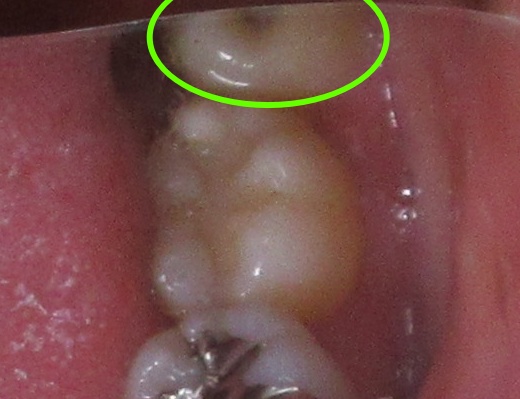

まずお口の中を確認してみると、左下の親知らずは頭が見える状態でした。